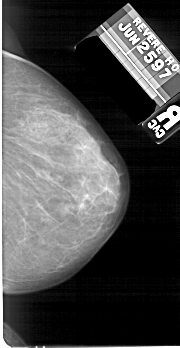

A_1673_1.RIGHT_CC

RIGHT_CC LINES 5206 PIXELS_PER_LINE 2686 BITS_PER_PIXEL 12 RESOLUTION 43.5 NON_OVERLAY